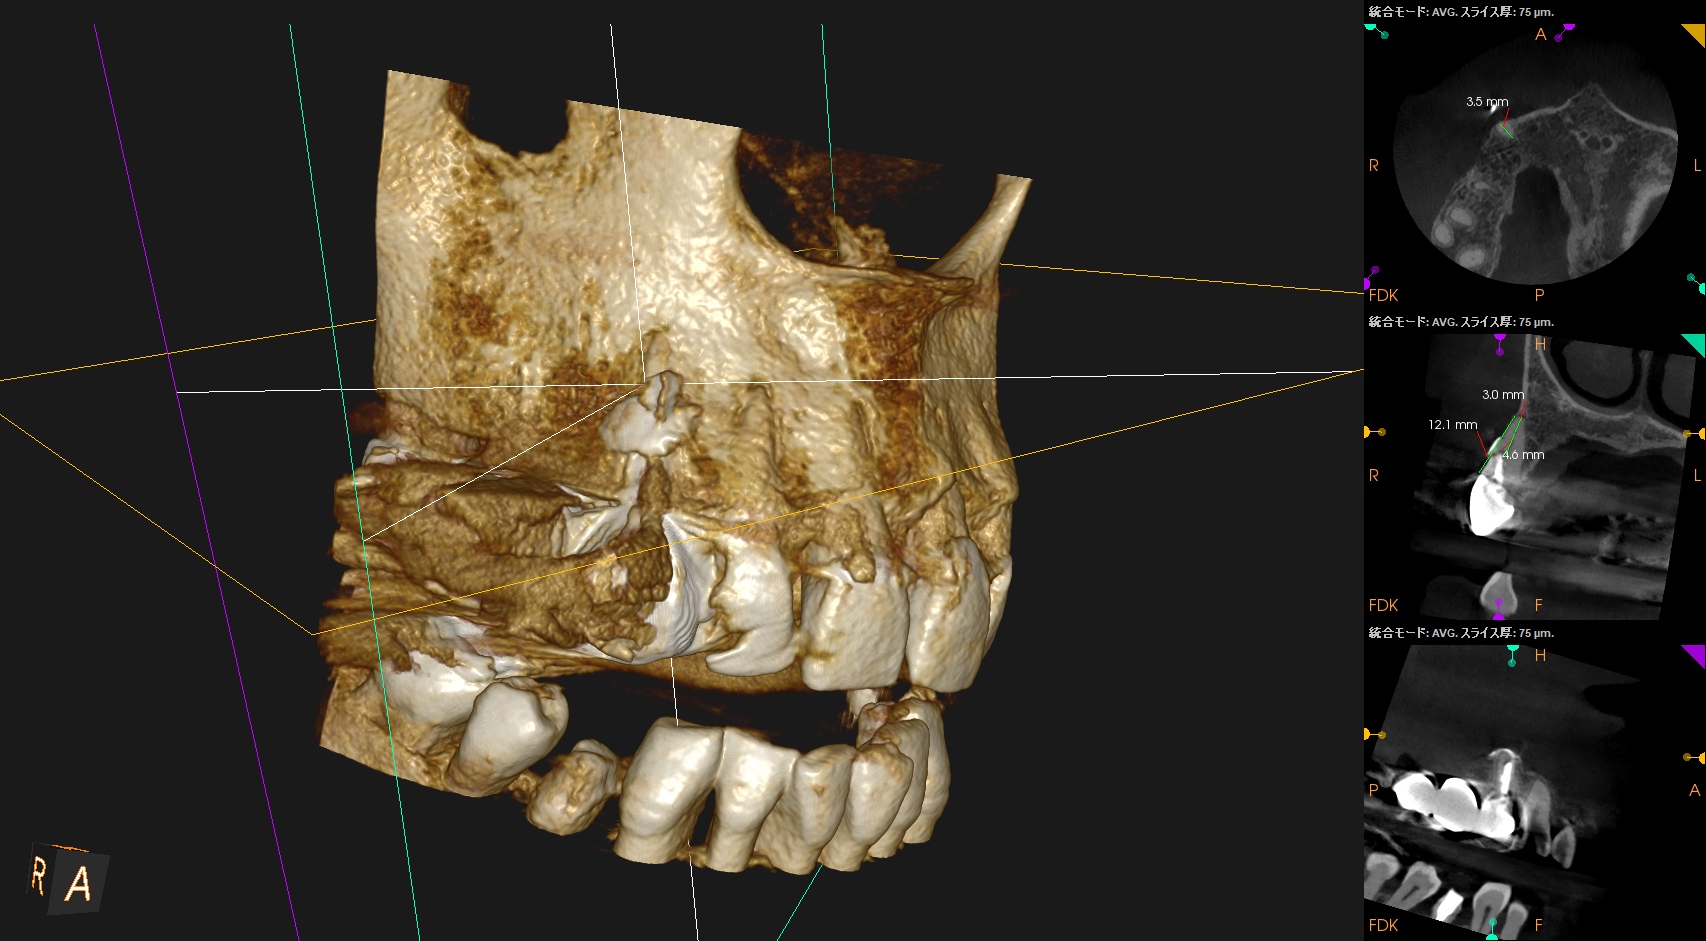

PA, CBCTを撮影した。

しょっぱい逆根管形成になったが主根管は確保されたので縫合して終了した。

根切した部分にはだいぶ骨が添加されているし、外部吸収も進展していないようだ。

ということでこの処置にはこれからも定期的な経過観察が必要である。